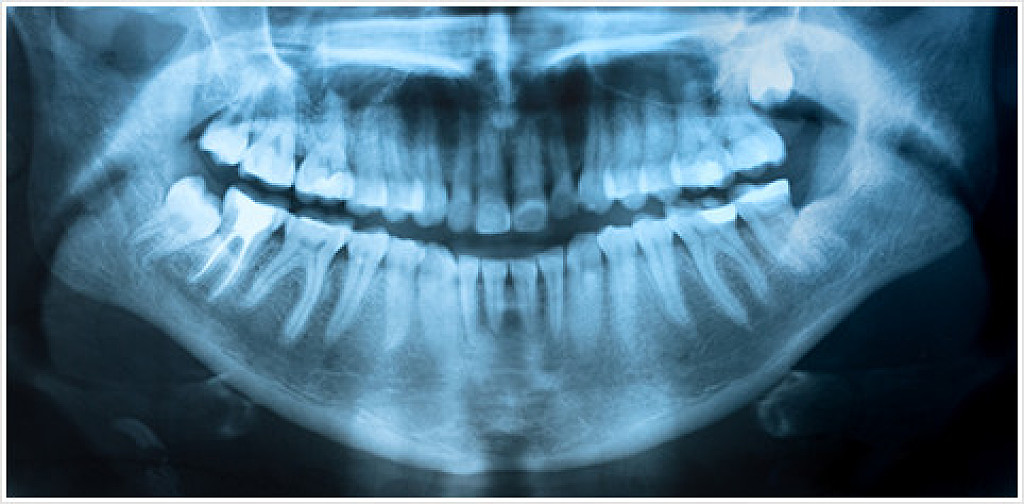

Digital X-rays don’t require any chemical processing

X-rays are a standard tool in the dental industry that we use to identify issues in the teeth, surrounding tissues, and jaw that would either be hard to see or hidden from a routine visual examination.

Some examples of problems we can spot with X-rays include tooth decay around restorations, deep cavities, jawbone infections, gum disease, abscesses/cysts, developmental abnormalities, and some types of tumors.

Chun Family Dentistry uses digital X-rays, because they have numerous benefits over their conventional counterparts. Digital X-rays don’t require any chemical processing, which means we get images faster and it’s easier on the environment. They also emit much less radiation, keeping you safe in our care!